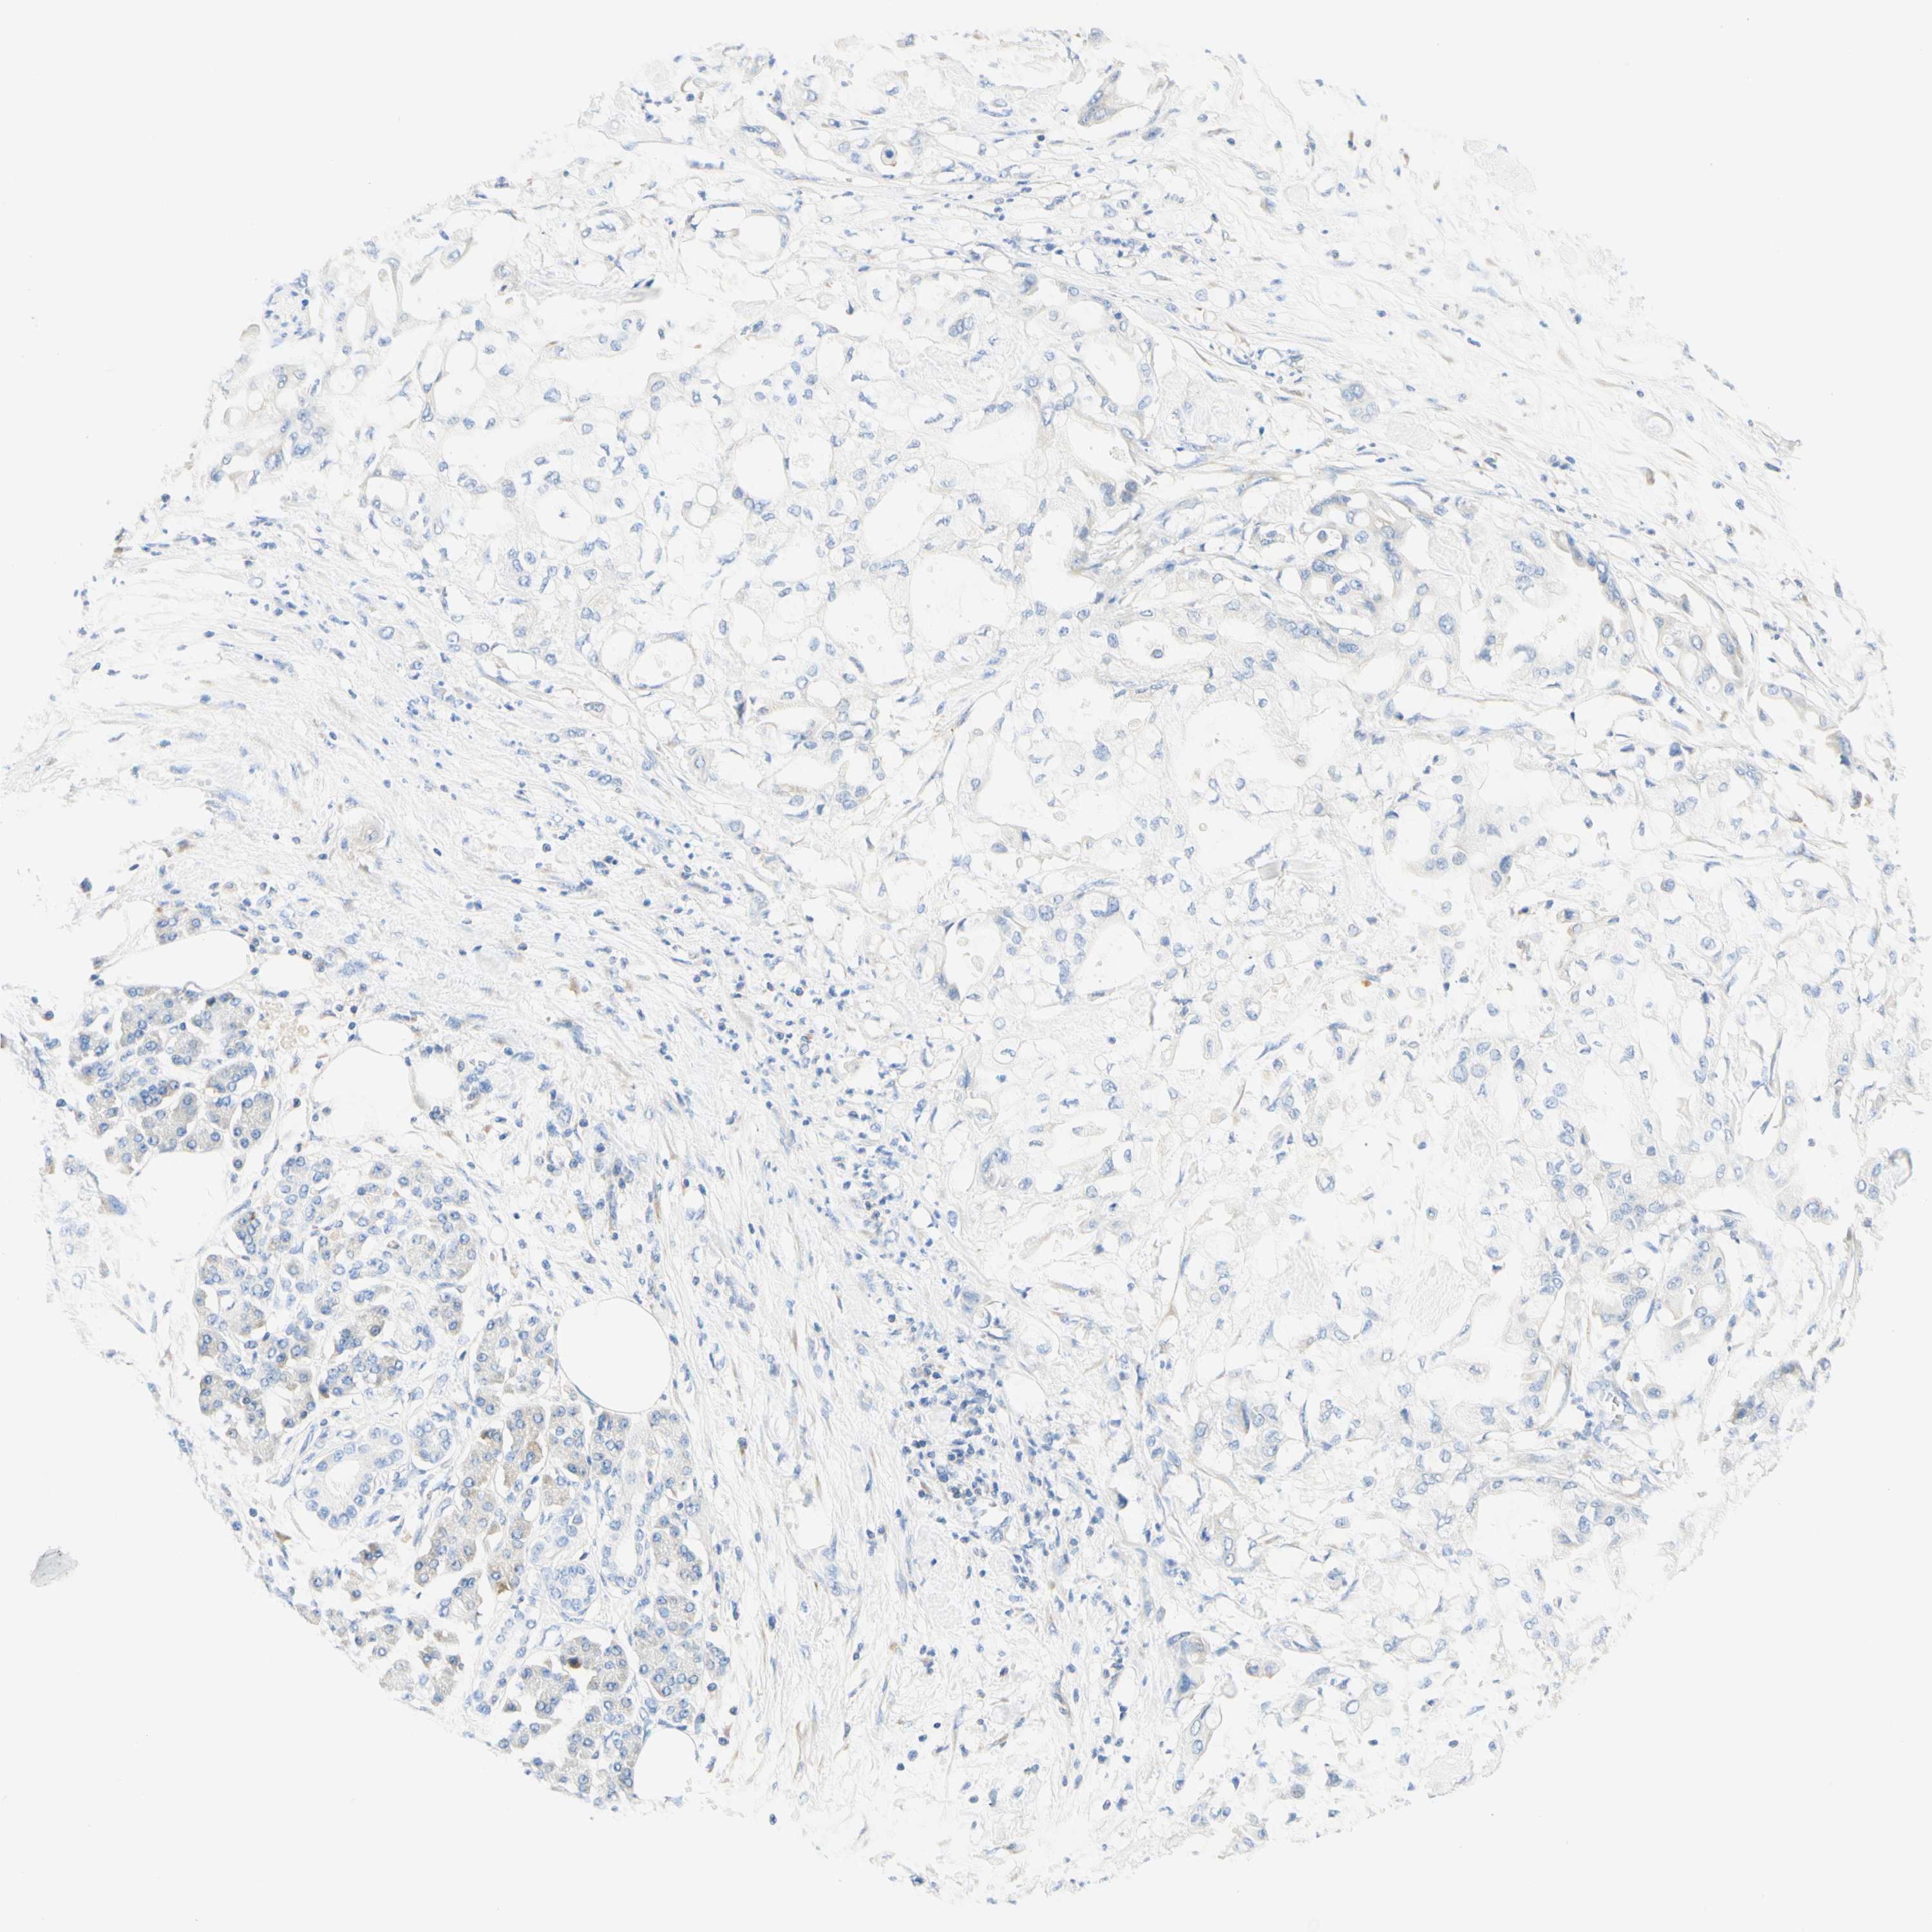

PANCREATIC CANCER - Protein expressioni

A mouse-over function shows sample information and annotation data. Click on an image to view it in a full screen mode. Samples can be filtered based on level of antibody staining by selecting one or several of the following categories: high, medium, low and not detected. The assay and annotation is described here.

Note that samples used for immunohistochemistry by the Human Protein Atlas do not correspond to samples in the TCGA dataset.

Antibody stainingi

Antibody staining in the annotated cell types in the current human tissue is reported as not detected, low, medium, or high, based on conventional immunohistochemistry profiling in selected tissues. This score is based on the combination of the staining intensity and fraction of stained cells.

Each image is clickable and will lead to virtual microscopy that enables deeper exploration of all samples and also displays staining intensity scores, fraction scores and subcellular localization as well as patient and tissue information for each sample.

Antibody HPA011157

Antibody CAB002223

Antibody CAB012978

Antibody CAB079960

Adenocarcinoma, NOS